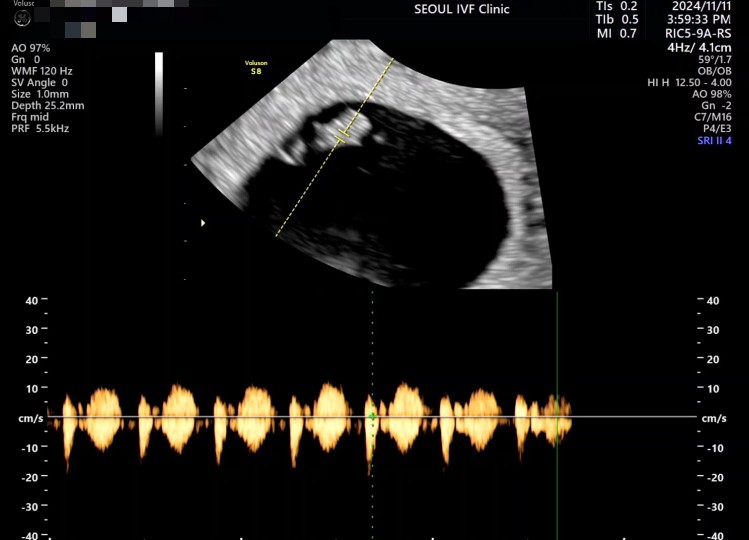

| 가슴 떨리는 임신 이야기를 공유해 주세요. | 안녕하세요. 다른 분들의 희망나눔 글들을 보면서 나도 언젠가 여기에 글을 쓸 수 있을까 생각해왔는데 이렇게 글을 적게 되어 매우 감격스럽습니다. 저희 부부는 결혼 후 일 년이 지났음에도 아이가 생기지 않아 난임검사를 하기 위해 22년에 서울아이비에프의원을 처음 방문했습니다. 큰 문제 없겠지 하고 받았던 난임 검사의 결과는 충격적이게도 남편에게 난임요인이 있다는 것이었습니다. 절망스러웠지만 우리 부부를 닮은 아이를 꼭 만나고 싶었기에 이경훈 원장님께 추천받은 남성난임 전문병원에서 남편이 1년여간 치료 및 수술을 받았습니다. 그리고 23년도 말, 새로운 시작을 해보기 위해 다시 이경훈 원장님께 돌아왔습니다. 원장님께서는 제 나이가 많지는 않아서 시도하면 생각보다 금방 아이가 생길 수도 있다고 하셨고, 그 말씀에 힘입어 기대를 품고 24년 1월부터 시험관 시술을 시작하게 되었어요. 그러나 기대만큼 아이가 빨리 제게 와주질 않았습니다. PGT 통과 배아가 잘 나오지 않아 이식 없이 채취만 여러 번 시도해야 했고, 과배란 과정 중에 난포가 비정상적으로 빨리 자라 주기가 취소된 적도 있었습니다. 힘든 채취 끝에 겨우 얻은 한 개의 PGT 통과 배아가 상태가 매우 좋다고 하셔서 첫 이식에 임신이 되는 건 아닌지 기대했으나, 절망스럽게도 착상조차 되지 않았습니다. 너무나 허탈하고 채취부터 다시 시작해야 해야 하는 것이 정말 막막했지만 이경훈 원장님께서 자궁내시경도 보자고 하시고, 다음 채취 때는 PGT검사 없이 이식 시도해보자고 하시는 등 다양한 고민과 적극 처방을 해주셔서 힘을 내어 다시 채취부터 해보기로 했습니다. 그리고 10월, 채취한 배아들에 PGT를 하지 않고 한 개의 배아를 이식하게 되었고 꿈만 같게도 이식에 성공하여 지금 8주 2일차가 되었습니다...! 피검사 결과를 보던 날 저만큼이나 환하게 웃으시며 축하해 주시던 이경훈 원장님의 모습이 아직도 생생합니다. |